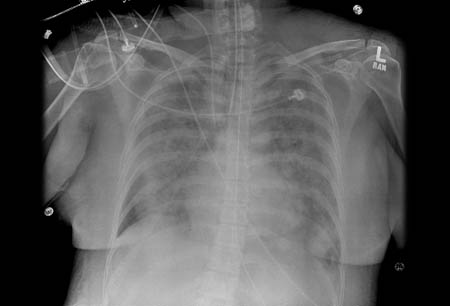

მწვავე რესპირატორული დისტრეს სინდრომი (ARDS)

ARDS მქონე პაციანტებში ბილატერალური ინფილტრატების გულმკერდის რენტგენოგრაფიული სურათი

ექიმ ლორეინ ვეარის პირადი კოლექციიდან; გამოიყენება ნებართვით